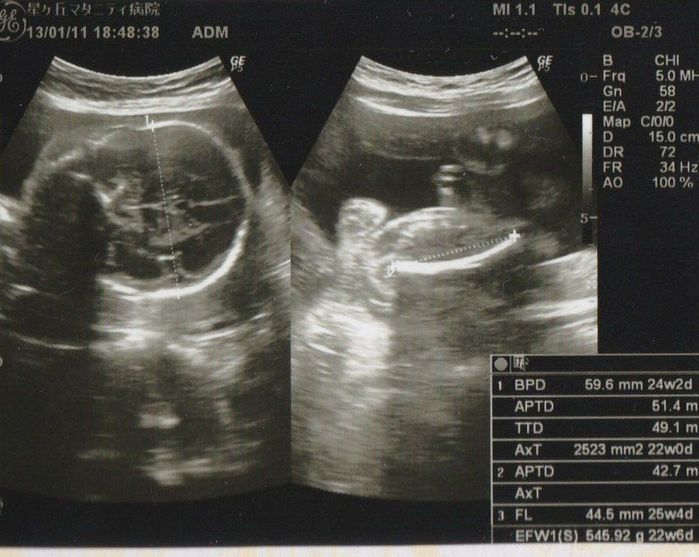

妊娠25週目のエコー写真

左側の写真は頭部の写真です。推定体重は645g、頭の大きさは約6cm。4週間前から比べると14mm程大きくなりました。まだ片手に収まる大きさでしょうか。右側の写真は大腿骨の写真です。この頃、性別がわかるか聞いてみると、「この丸いのが男の子の象徴かな? どうかな~? 」という返答でした。